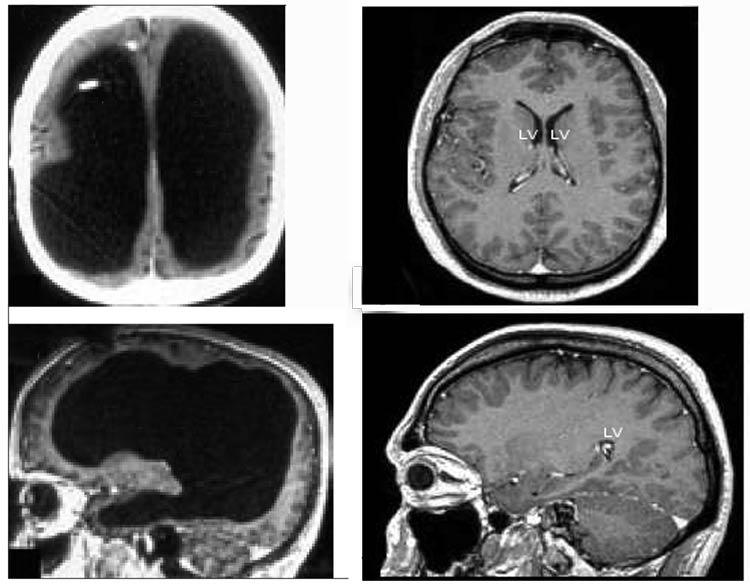

Those who seem to have large memory stores (savants; Section 6) usually do not have oversize heads. And it is also noted (Section 9) that some microcephalics have normal intelligence, so may not necessarily have small memory stores. A recent book (Bateson & Gluckman 2011) brings to attention an amazing reduction in brain mass in some who were treated in early childhood for enlarged ventricles ("water on the brain"), yet now retain or exceed normal intelligence (Feuillet et al. 2007).

Scan of brain with enormous ventricles

Brain scan of Feuillet hydrocephalic patient as adult at left, compared with normal subject on the right

This dramatically affirms an earlier, more extensive, study reported by neurologist John Lorber (Lewin 1980). Most amazing was a student at Sheffield University, referred to Lorbor, simply out of interest, since he had a slightly larger than normal head. Lorber stated:

"There's a young student at this university who has an IQ of 126, has gained a first-class honors degree in mathematics, and is socially completely normal. And yet the boy has virtually no brain. When we did a brain scan on him, we saw that, instead of the normal 4.5 centimeter thickness of brain tissue between the ventricles and the cortical surface, there was just a thin layer of mantle measuring a millimeter or so. His cranium is filled mainly with cerebrospinal fluid." -- "I can't say whether the mathematics student has a brain weighing 50 grams or 150 grams, but it's clear that it is nowhere near the normal 1.5 kilograms, and much of the brain he does have is in the more primitive deep structures that are relatively spared in hydrocephalus. There must be a tremendous amount of redundancy or spare capacity in the brain, just as there is with kidney and liver. The cortex probably is responsible for a great deal less than most people imagine."